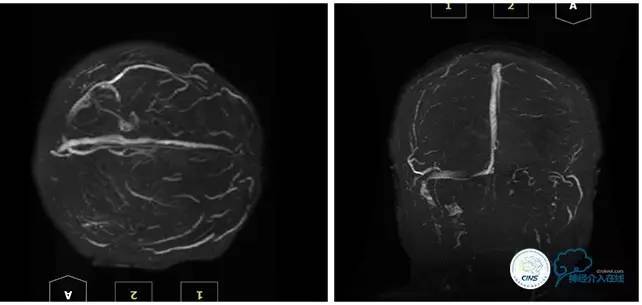

MRV

2016-05-20 MRV

病史:患者于1年余前,因头部外伤在外院行头颅CT提示:未见异常。约3月后患者出现头痛、发作性意识丧失,在当地医院行头颅CT及MRI提示:未见明显异常。诊断为外伤性癫痫,予以对症治疗,未见明显好转。6月余前,无明显诱因出现鼻腔漏液,予以保守治疗,此后鼻腔间断漏液,漏液后头痛缓解。13天前因高热、恶心、呕吐在外院诊断为颅内感染(肺炎链球菌),予以抗炎等对症治疗2周后鼻漏停止,体温正常,CSF常规、生化正常,但头痛仍未缓解,转入我院神经内科治疗。反复腰穿颅内压450-500mmH2O左右,脑脊液常规及生化均正常。颅脑CT及MRI、MRV提示:左侧顶叶硬膜下血肿,鼻窦炎、乳突炎、左侧横窦、乙状窦闭塞、右侧横窦、乙状窦狭窄。予以华法林抗凝治疗2周,维持INR2-3,患者头痛仍无明显缓解,颅内压无下降,转入我科。

诊断:1、右侧横窦、乙状窦狭窄;2、硬膜下血肿(左侧顶);3、继发性癫痫;4、脑脊液鼻漏;5、颅内感染;6、乳突炎;7、鼻窦炎。